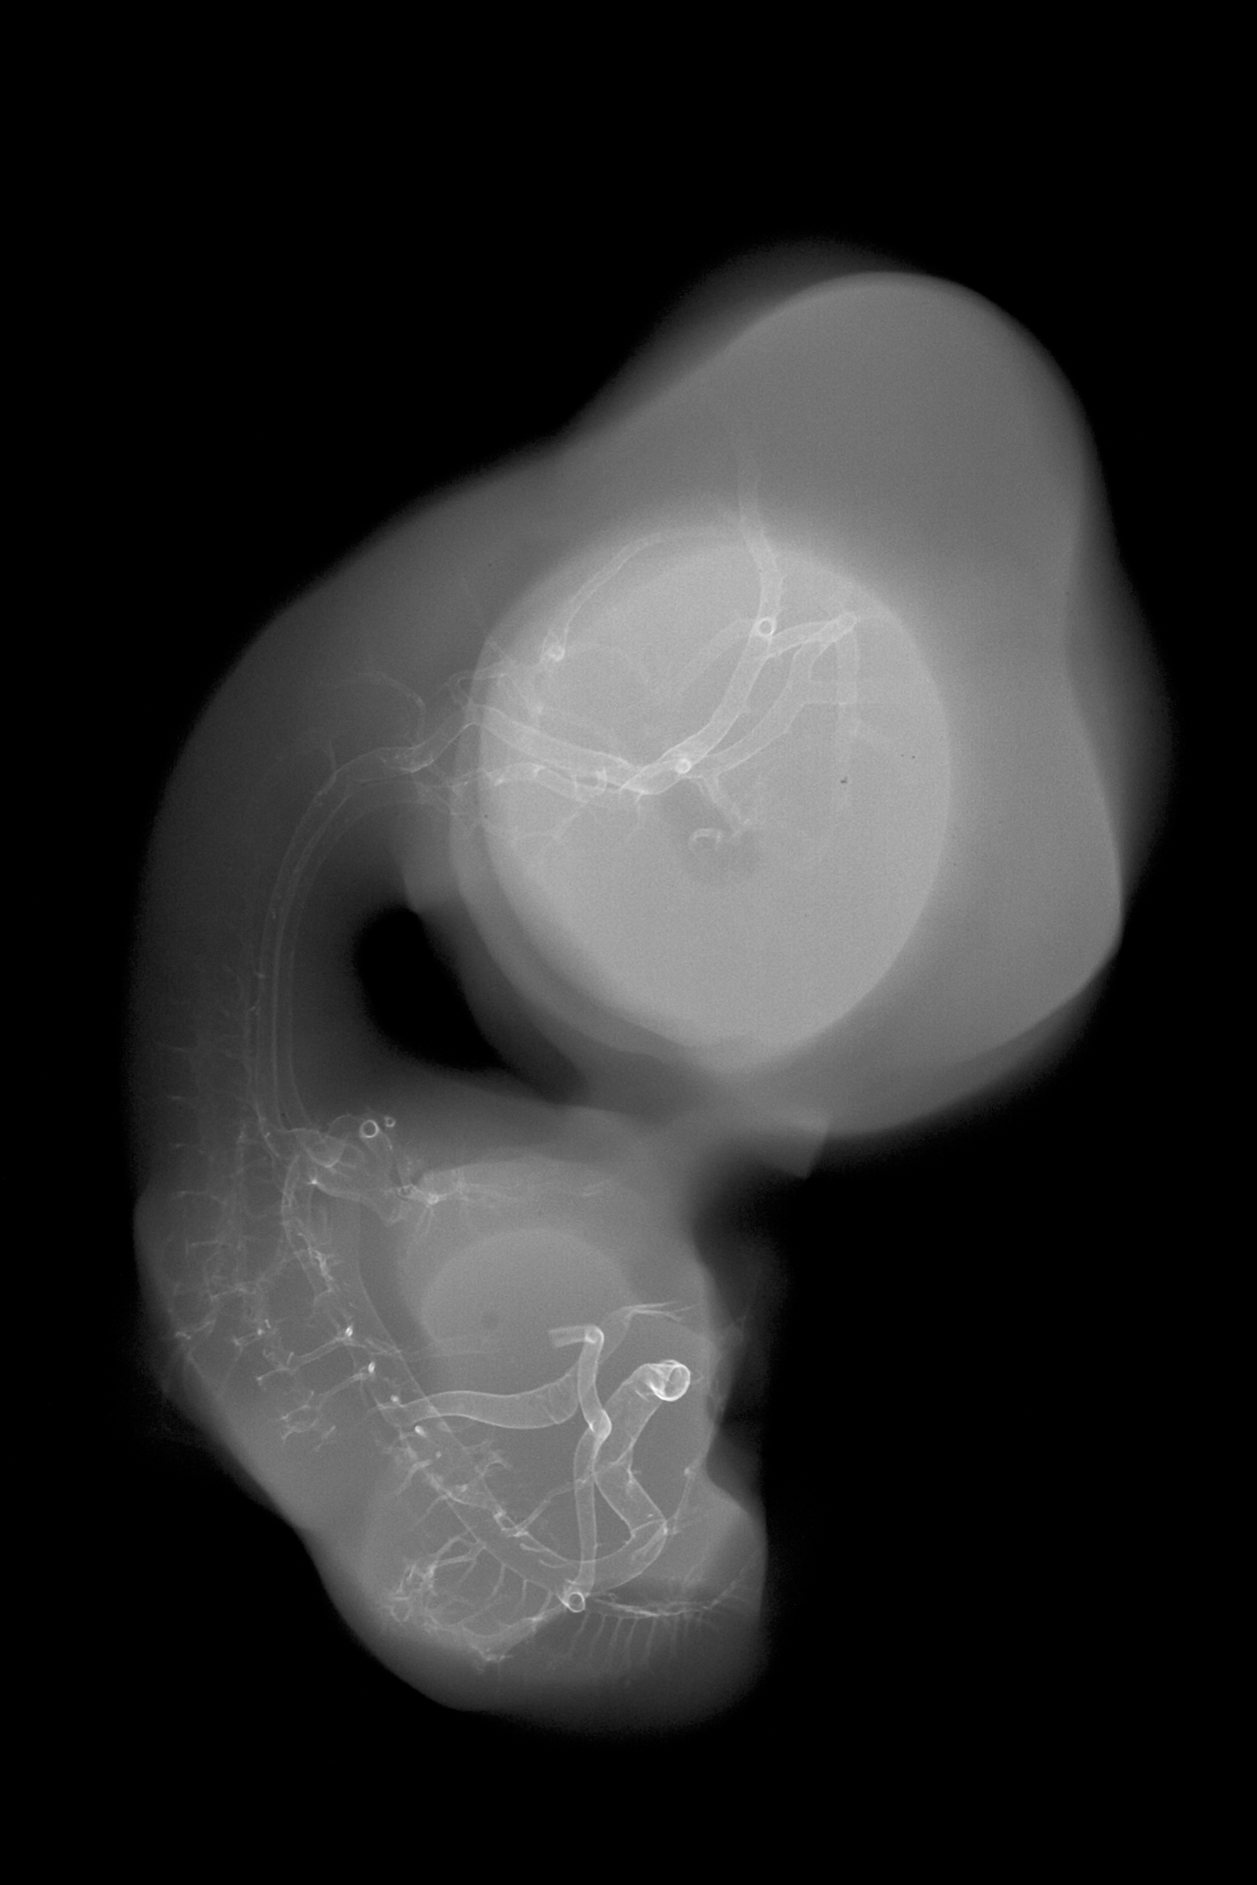

Chick Embryo Microangiography

Hamburger-Hamilton (HH) Stage 30 (approx. 6.5 days)

Stereo X-Ray Micrographs